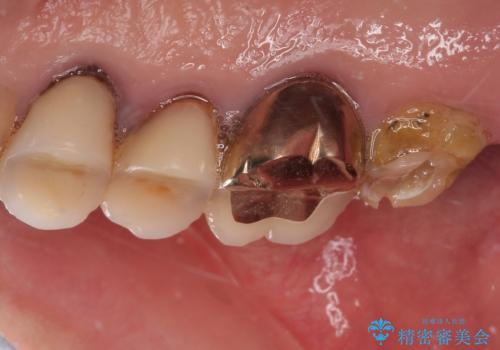

- 食事が取れないほどの激痛で、インプラント治療を希望して来院された患者様です。

近医にてクラウンを除去してもらった状態での来院でした。

遠心が歯根破折しており、歯槽骨が著しく吸収している状態であったため、抜歯即時でのインプラント埋入は断念し、2ヶ月ほど待機してから埋入することとしました。